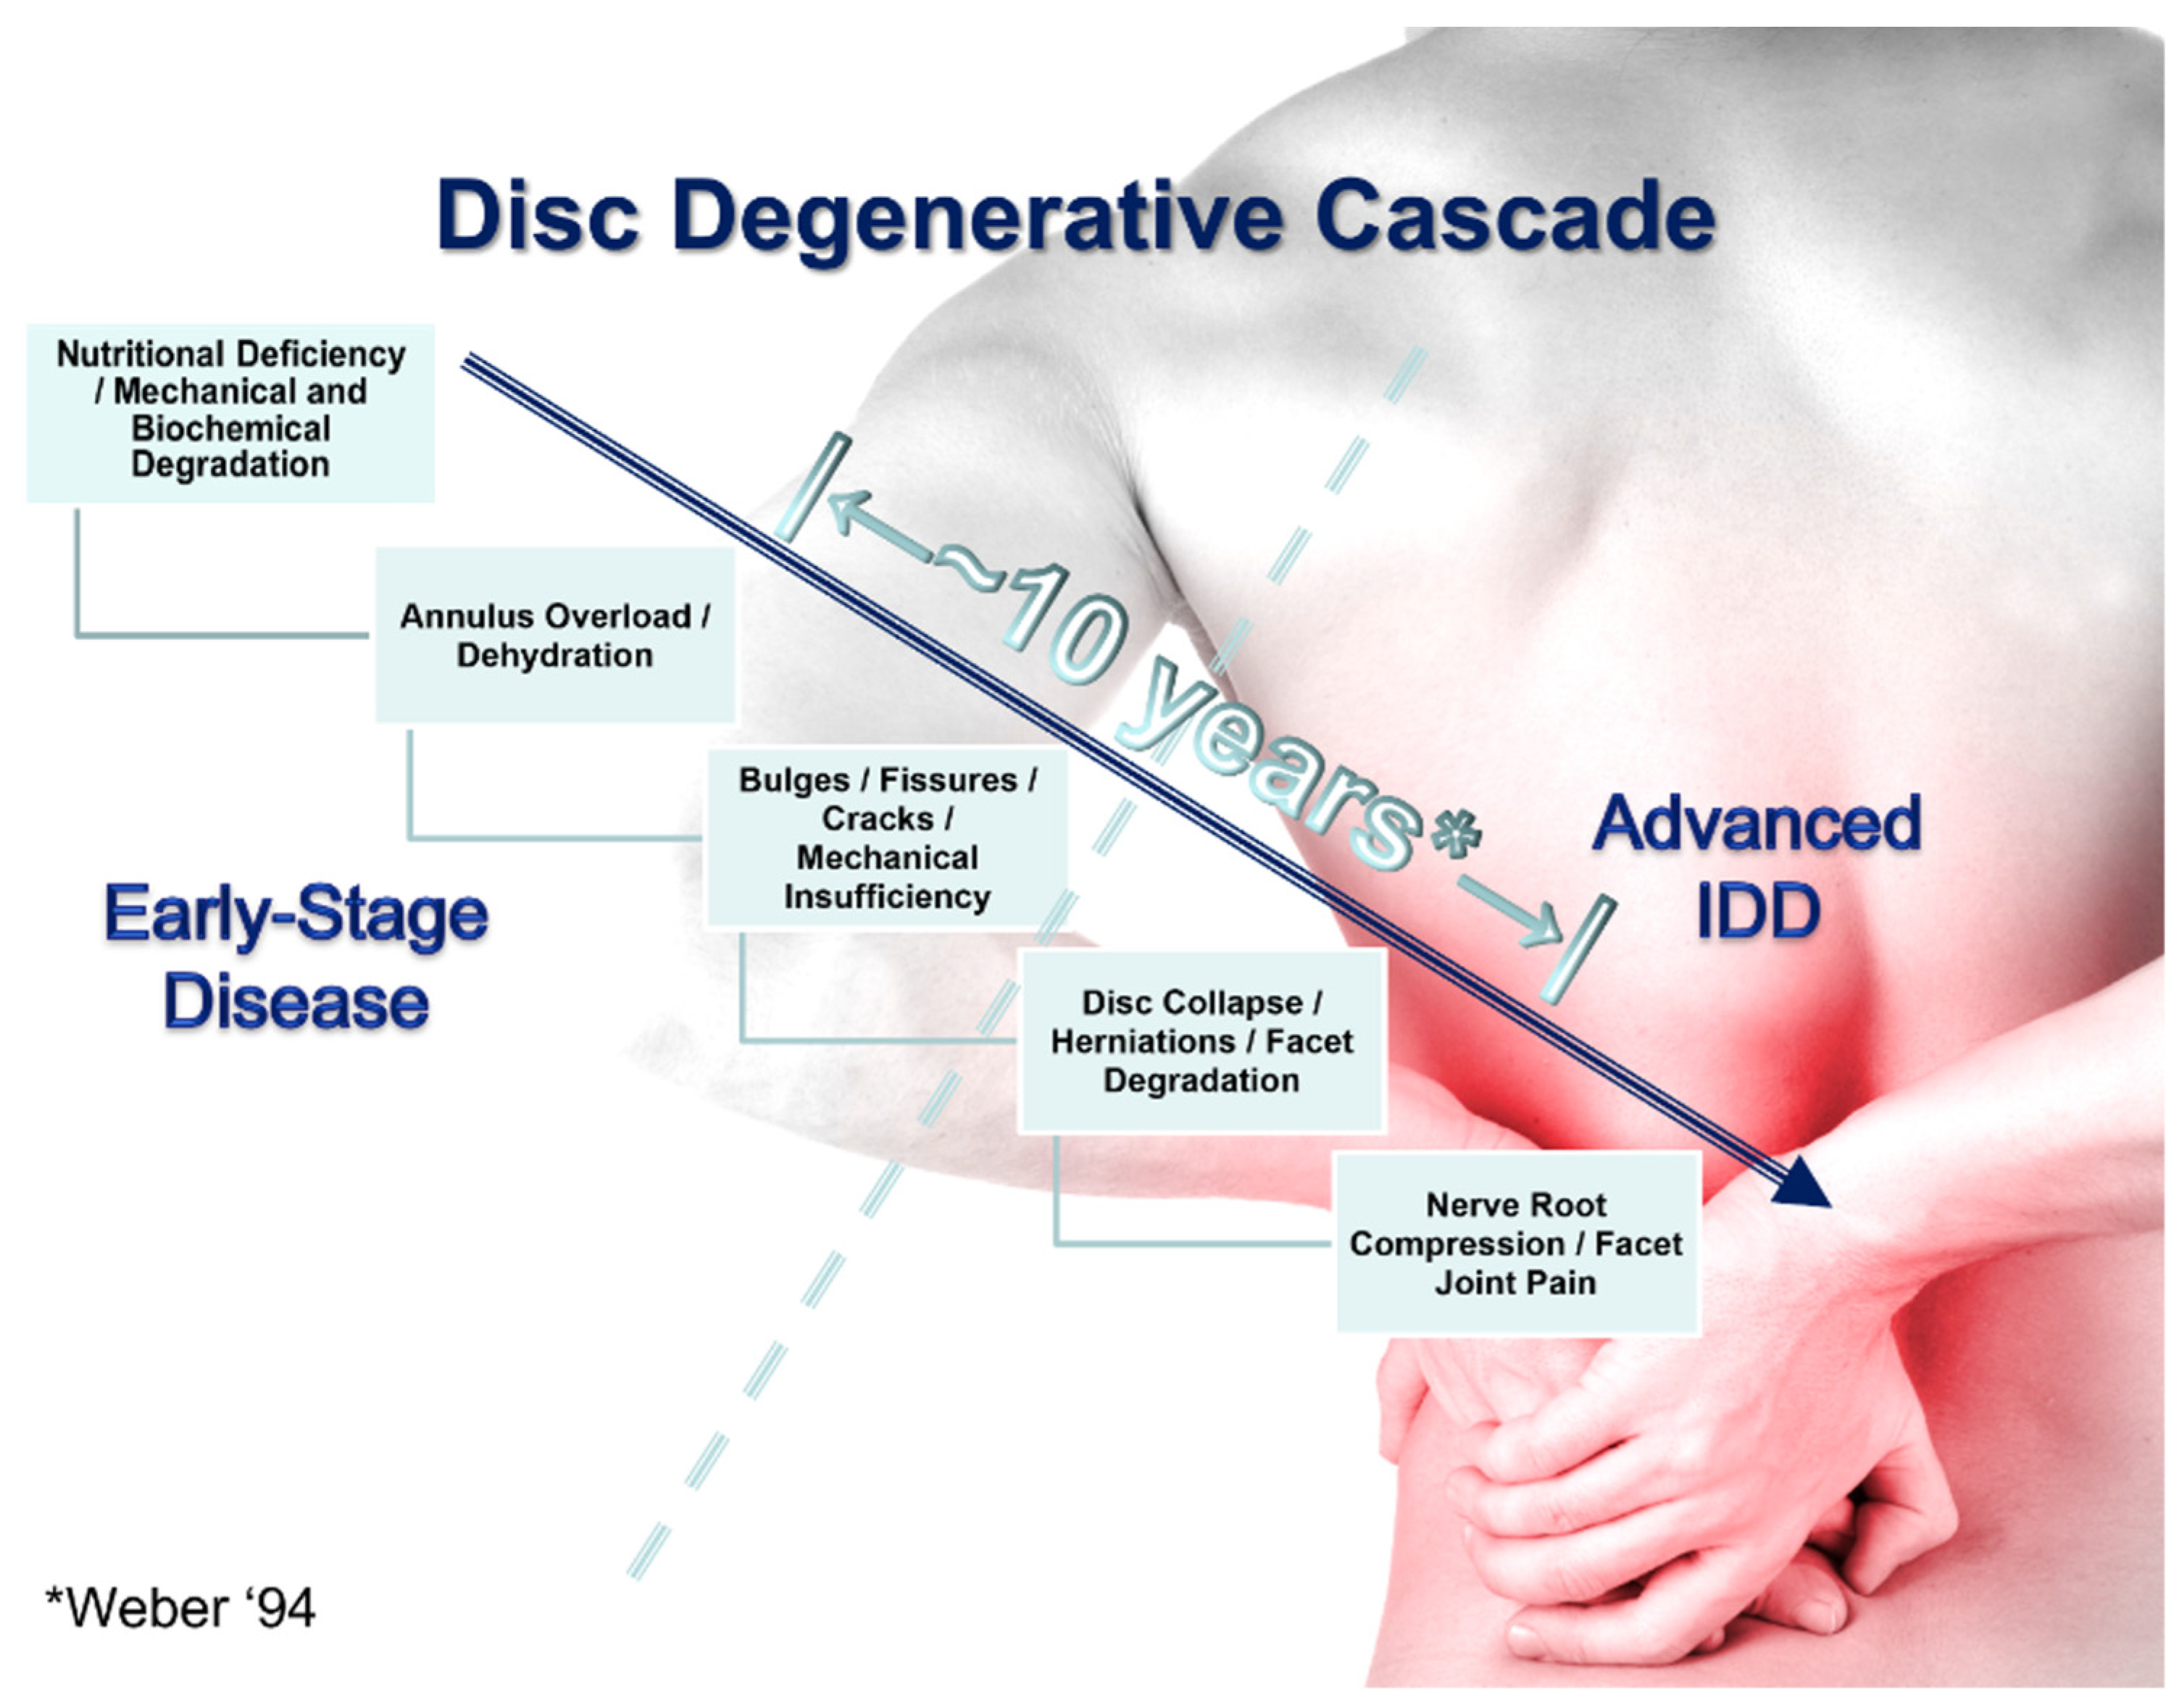

3.1. The Role of Mechanical Strength Deterioration in the Pathogenesis of IDD